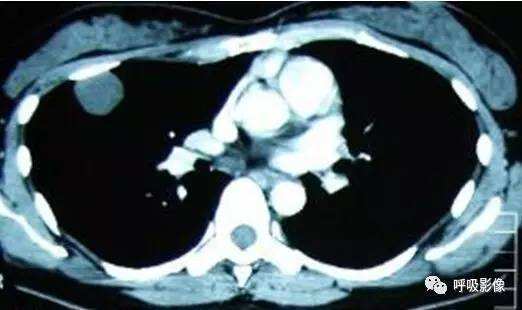

胸部CT示双肺多发结节影,强化明显,内见明显坏死,提示血供丰富。

转移瘤多具有原发肿瘤特点,本例转移瘤为生殖源性肿瘤,盆腔附件包块穿刺活检细胞学检病理均查见恶性肿瘤细胞,结合转移灶坏死、强化明显,需考虑绒毛膜癌缠医可能。

胸部CT双肺多发结节影,强化明显,内见明显坏死,提示血供丰富,这是诊断关键。